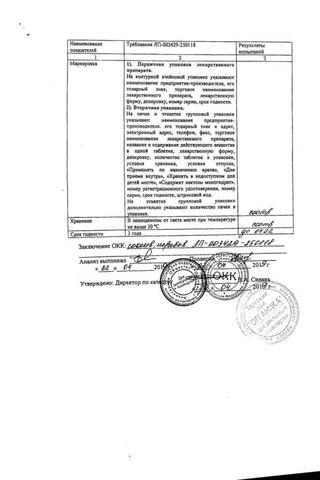

Аллопуринол таблетки 300 мг 30 шт

Аллопуринол: Состав

Таблетки белого или белого с желтоватым оттенком цвета, круглые, плоскоцилиндрические, с риской и фаской.

1 таб.

аллопуринол 100 мг

Вспомогательные вещества: целлюлоза микрокристаллическая (МКЦ-101 Премиум) - 54 мг, крахмал кукурузный - 25 мг, карбоксиметилкрахмал натрия - 10 мг, повидон К25 - 8 мг, кремния диоксид коллоидный - 1 мг, магния стеарат - 2 мг.

10 шт. - упаковки ячейковые контурные (1, 2, 3, 4, 5, 6, 7, 8, 9 или 10 шт.) - пачки картонные.

14 шт. - упаковки ячейковые контурные (1, 2, 3, 4, 5, 6, 7, 8, 9 или 10 шт.) - пачки картонные.

25 шт. - упаковки ячейковые контурные (1, 2, 3, 4, 5, 6, 7, 8, 9 или 10 шт.) - пачки картонные.

30 шт. - упаковки ячейковые контурные (1, 2, 3, 4, 5, 6, 7, 8, 9 или 10 шт.) - пачки картонные.